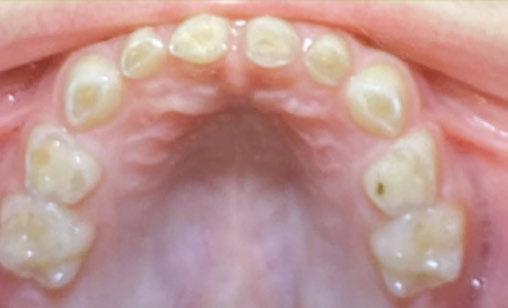

An 8-year-old Hispanic male presented to our private practice in Miami, Florida with the chief complaint of a missing front tooth (Figure 1). Upon review of his medical history, the mother revealed that her son had Autism Spectrum Disorder and confirmed that his condition was severe. This patient did not take

any medications, was nonverbal, avoided eye contact with any staff member including the treating pediatric dentist, did not sit in the dental chair, and was constantly tapping his ears. No dental radiographs were obtained due to his uncooperative behavior. For the dental exam, the mother agreed and consented with placing him in a passive restraining device. With a limited visualization of his oral cavity, a mixed dentition was noted. The maxillary right permanent central incisor was absent. No significant pathology was found in his oral soft tissues. Dental caries was found on both primary and permanent molars. A decision was made to complete dental treatment using general anesthesia as a behavior management technique at the local children’s hospital.

At the postoperative consultation with the mother, we told her the tooth’s complete root formation might prevent its eruption. Orthodontic extrusion of the incisor was ruled out due to his behavior. A conservative approach with observation only was elected as treatment modality. This patient returned for follow-up appointments at ages 10, 11, 12, and 13. During all these visits, the maxillary right permanent central incisor had not erupted. At age 14, due to recurrent dental caries, the patient was taken to the local children’s hospital for dental rehabilitation again. During this second hospitalization, we noticed that the right maxillary central incisor was partially erupted into the oral cavity (Figure 4).